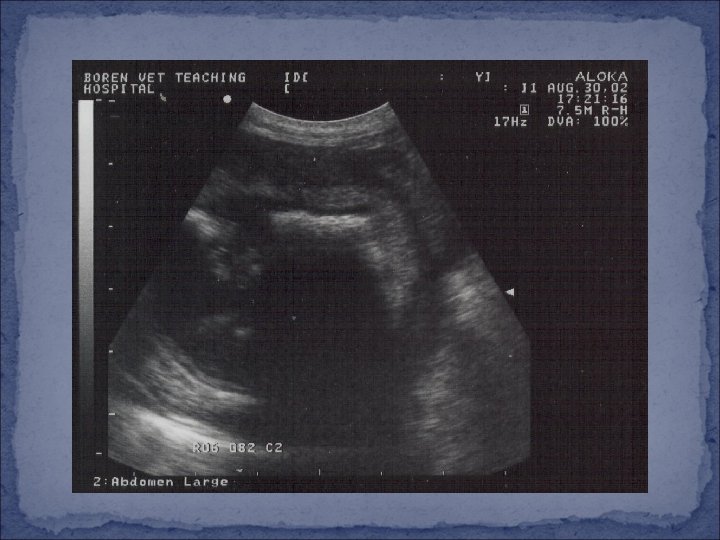

Diagnosis �Species, gender, history, clinical signs �Physical examination �Analysis of urine �IF possible…. incomplete obstruction or cystocentesis �Type of crystals/stones �Ultrasound �Urethra, bladder, kidneys, abdomen �Radiographs (x-rays) �Endoscopy